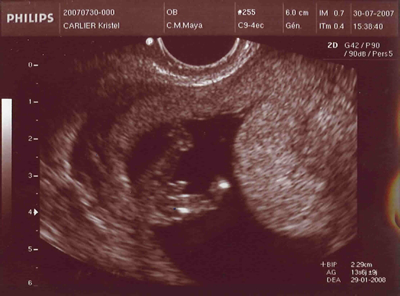

Ma première echographie...

Voici une echo révélatrice...